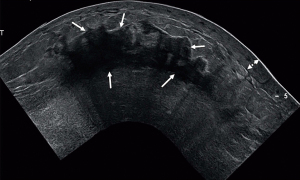

One commonality among IBC patients is a history that included evaluation with mammography that was reviewed as normal or no mass was identified. Indeed, in the study by Kamal et al., a review of images reveals that simple and malignant forms of mastitis have many signs in common (20). Mammographic signs were considered less discriminating than ultrasonography for identifying malignancy. Diffuse skin thickening and increased density favored malignant mastitis, whereas dilated retroareolar ducts and characteristic calcification patterns favored noninfectious forms. All of the patients with IBC had skin thickening on ultrasonography, but only 54% had skin thickening identified on mammography (20). However, skin thickening can also be present in benign mastitis (Figure 3). In the study by Dabi et al., the presence of a mass (present in 21/45 cases, malignant in 15/20, P=0.04), microcalcifications (present in 20/45 cases, malignant in 16/20, P=0.04) or focal asymmetry on mammography (present in 9/45 cases, malignant in 8, P<0.001) were all significantly associated with malignant disease, but these signs were not present in all cases (17). Overall, relative to patients with benign disease, patients with a malignant lesion were more likely to have skin thickening (58% vs. 32%, P=0.05) and more lymph nodes suspected of harboring disease at clinical examination (50% vs. 8%, P<0.001). Patients with malignant disease were also significantly older (P=0.022) and had significantly larger palpable masses (8.1 vs. 4.1 cm, P<0.001). Conversely, precise delimitation of the mass on ultrasonography was significantly associated with benign lesions. In work from Le-Petross et al. (21), primary breast lesions were more often visible on sonography than on mammography. An interesting sonographic feature best demonstrated on extended-field-of-view images was a linear infiltrative pattern that dissected through the breast parenchyma with loss of normal architecture (Figure 4). Critically, targeting this area of focal linear infiltration in the absence of a discrete mass on sonography yielded a diagnosis of cancer and enabled evaluation of biological markers in this study (21). Moreover, primary breast lesions on a background of extensive diffuse edema were more likely to be detected on MRI (when contrast is used) than on ultrasonography or mammography (Figure 5), and this additional information can assist in identifying a target for biopsy (21). Yang et al. reviewed and compared mammography, ultrasonography, MRI, and positron emission tomography/computed tomography (PET/CT) for their ability to identify breast parenchymal lesions, both to aid in the radiographic diagnosis and to guide clinicians regarding definitive biopsy (22). Among the 80 patients included in that study, 75 (94%) had undergone mammography, 76 (95%) sonography, 33 (41%) MRI with contrast, and 24 (30%) PET/CT. A primary parenchymal breast lesion was found in 60 patients (80%) on mammography (mass or calcifications), 72 (95%) on sonography (mass or architectural distortion), 23 (96%) on PET/CT (hypermetabolic lesion), and 33 (100%) on MRI (enhancing lesion). These findings highlight the value of MRI in the work-up of IBC to guide biopsy when earlier imaging has failed to reveal a dominant lesion or shows abnormal but inconclusive results. Notably, 97% of the women in this study had non-fatty breasts despite being largely postmenopausal. The authors speculate that the breast parenchymal background may have contributed to the poor visibility of a primary breast parenchymal lesion on mammography in 15 patients (20%). Also, the basic imaging findings associated with IBC in that study agreed with those described by others (23-30), namely, diffusely increased parenchymal density (now termed global asymmetry according to the ACR BIRADS lexicon (31), trabecular distortion, and skin thickening on mammography. The same group undertook an expanded analysis focusing on MRI and identified a very high likelihood of detecting a breast parenchymal lesion with MRI (98%, n=80) compared with 68% on mammography. Among patients with a breast parenchymal lesion, the most common MRI finding was a mass or multiple masses (57 of 78, 73%) (22). Masses were often multiple, small, and confluent (47 of 57, 82%); mass margins were irregular (43 of 57, 75%); and had a heterogeneous internal enhancement pattern (47 of 57, 82%). Kinetic analysis revealed a delayed washout pattern in 66 of 78 tumors (85%). MRI showed skin thickening in 74 of 80 breasts (93%), whereas mammography showed skin thickening in 56 of 78 breasts (72%) (22).